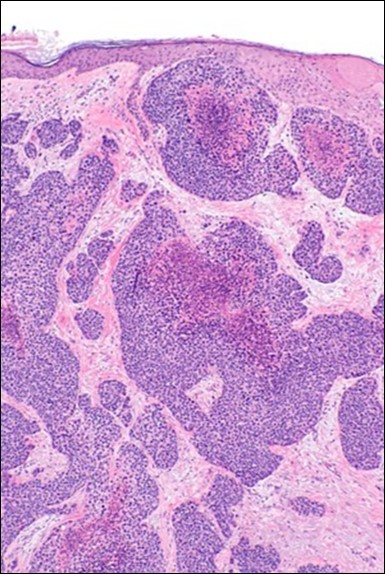

Granular arrangement of malignant cells and intercellular bridges are conspicuous with the demonstration of nuclear atypia, pleomorphism, prominent mitosis and tumour necrosis. A peripheral palisade is discernible within the cellular aggregates. Mitotic figures are common and can be quantified as up to 12 mitosis/ high power field. Tumour differentiation can prominently be of the ductal category with the demonstration of intra-cytoplasmic lumina. Comedo type tumour necrosis is evident along with foci of squamous differentiation The neoplasm is reactive to periodic acid Schiff ‘s (PAS) stain. (Figure 1, Figure 2, Figure 3, Figure 4, Figure 5, Figure 6, Figure 7, Figure 8, Figure 9, Figure 10, Figure 11, Figure 12, Figure 13.

Figure 1.Solid aggregates of tumour cells and duct structures in eccrine porocarcinoma (14).

Figure 3.Cohesive accumulations with numerous ductular articulations of carcinoma cells in eccrine porocarcinoma (15).

Figure 5.Sweat glandular articulations and malignant cellular aggregates with cystic spaces in eccrine porocarcinoma(17).

Figure 6.Epidermal continuity with aggregates of atypical, solid and cystic epithelial cell nests in eccrine porocarcinoma (18).